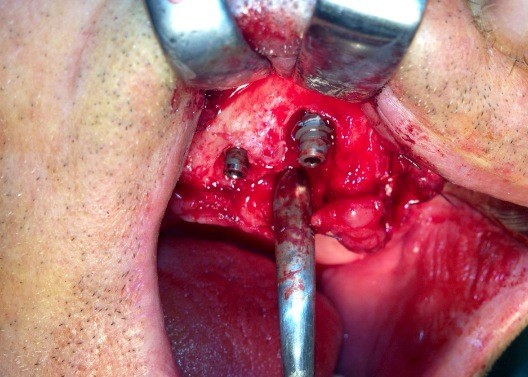

Implantologia avanzata con contestuale rimozione impianti e cisti

Video di una Parte dell'intervento in cui si puo' vedere la comunicazione tra impianti rimossi e pavimento nasale.